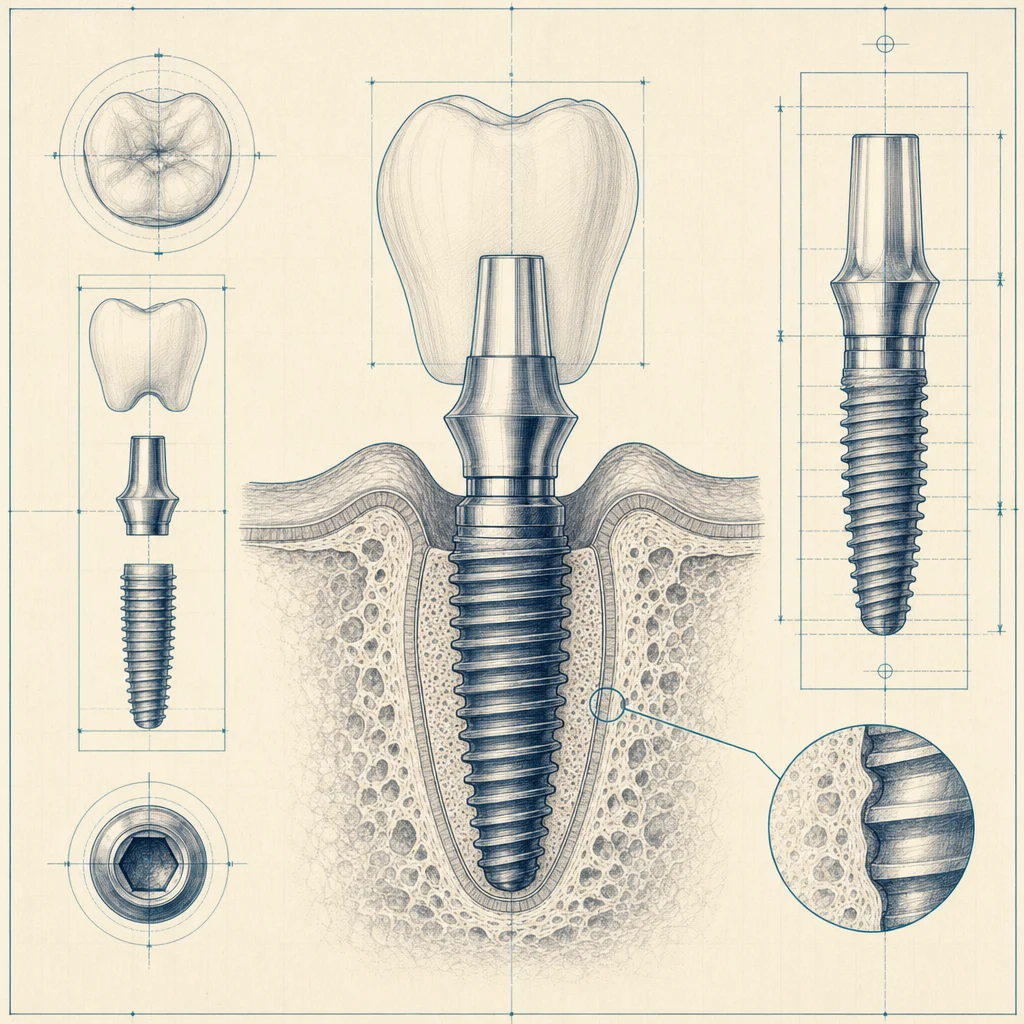

단계 2: 픽스처 식립 (1차 수술)

국소마취 하에 잇몸을 절개하고 인공뿌리(픽스처)를 식립합니다. 시술 자체는 한 개당 약 30~60분 소요됩니다. 골이식이 함께 진행되면 시간이 더 길어집니다.

식립 단계의 정밀도를 위해 멸균된 수술 키트가 단계별로 준비됩니다.

식립한 픽스처가 잇몸뼈와 단단히 붙는 데 2~3개월 정도 시간이 필요합니다. 이 기간 동안에는 가운데에 임시치아(임시 어버트먼트)를 끼우거나, 상황에 따라 임시 보철을 사용합니다.

단계 4: 보철 (크라운) 제작·장착

골융합이 확인되면 인상(본)을 떠서 보철물을 제작합니다. 2~3주 후 최종 보철물을 장착하면 시술이 완료됩니다.

- 어버트먼트(연결부): 픽스처와 보철을 잇는 부품